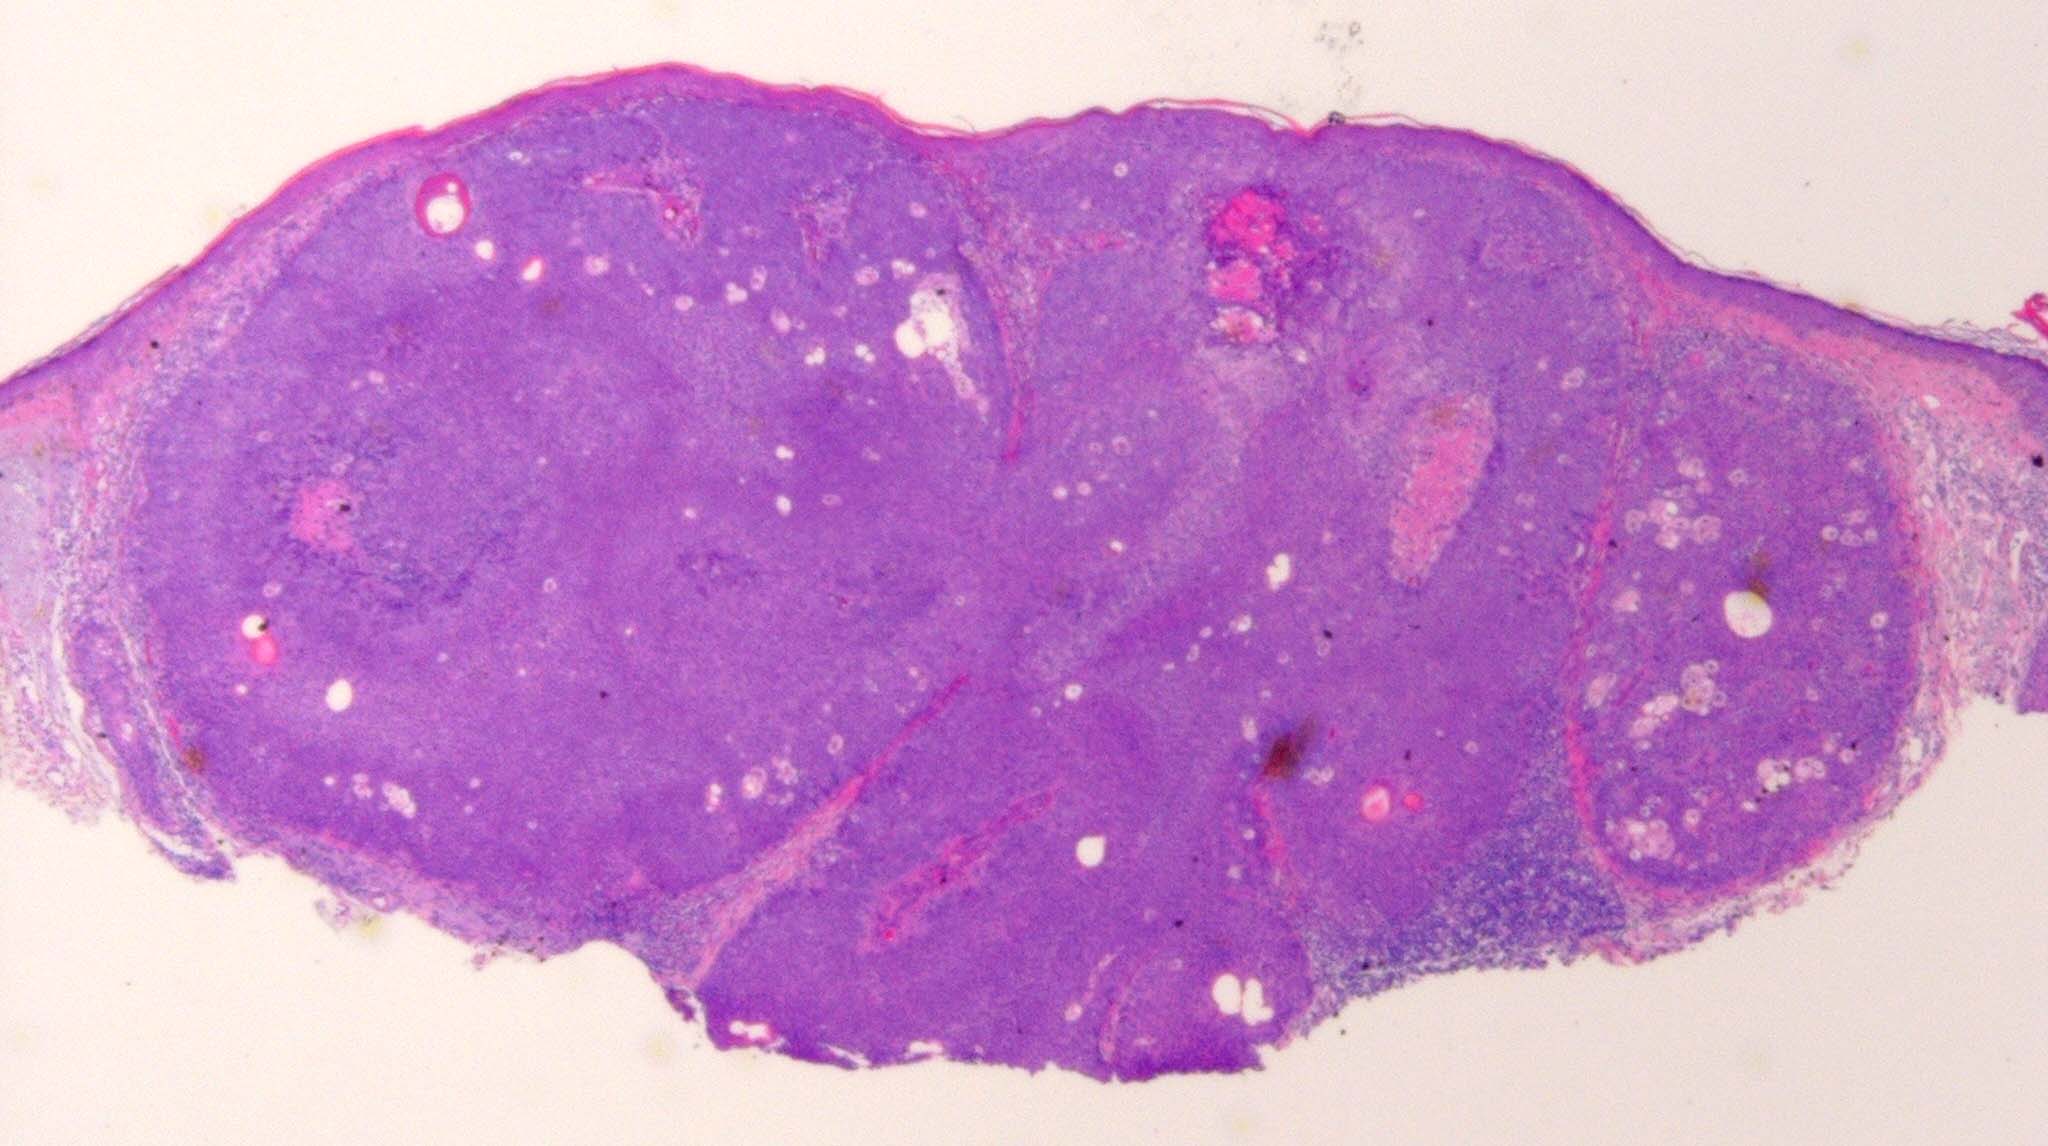

Sebaceous adenoma = غدوم دهني